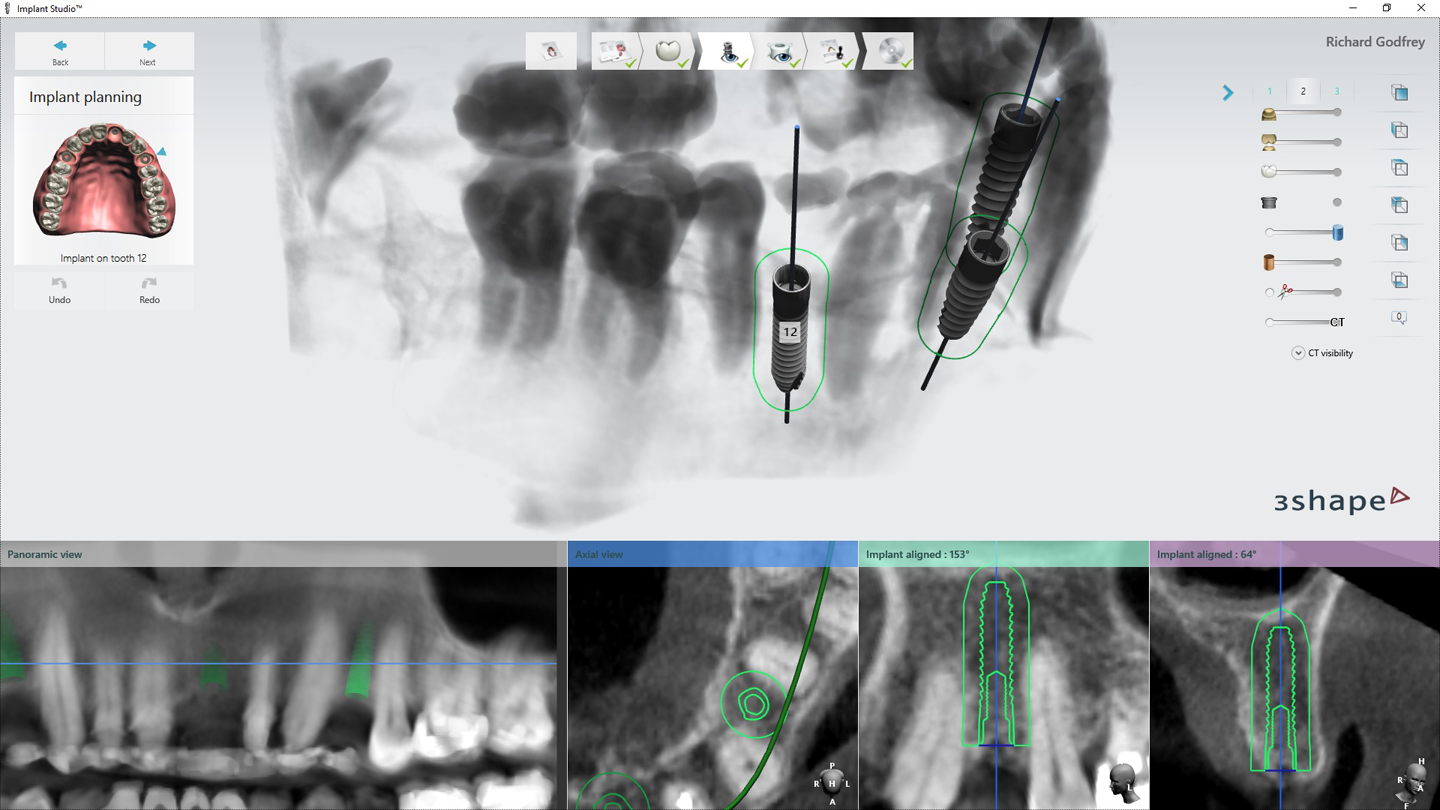

Implant dentistry is no different. Using 3Shape software (Implant Studio and Dental Designer), the entire restorative team (lab, restoring doctor and surgeon) can plan the surgery and restorative options based on the planned implant placement. Benchtop testing is showing fully guided implant surgery places the implant within .1 mm in all directions of planned placement. This certainly allows for the ability to place better temporary restorations or healing abutments than what has been used in the past.

2. This patient was then scanned with a 3Shape TRIOS intraoral scanner. The resulting color scan is shown in Figure 3. This scan was then pulled into 3Shape Implant Studio and aligned with the DICOM data, and placement of three BioHorizons Implants was planned. Tooth position #12 was planned with a 3.0 mm x 15.0 mm implant. In Figure 4 you can see the root formations for teeth 11 and 13 created a limited space situation.

Fig. 3 Fig. 4